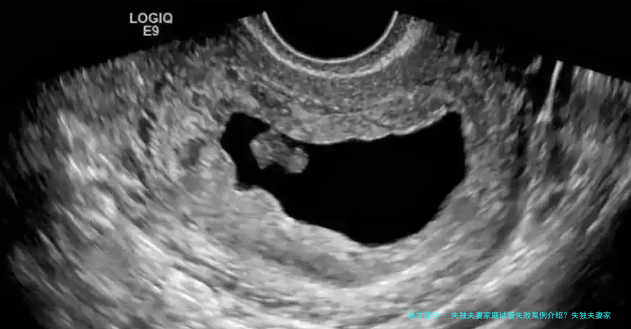

李女士在有所失唯一的孩子后,决计通过试管婴儿技术再次怀孕。她选择了本地一家有声誉医院进行试管手术。然而,经非常多次尝试,李女士却一向没有能够成功受孕。医生通知她,跟着年龄的增多,她的卵巢功效渐渐减少,试管婴儿的成功率同样会受到影响。

张老师在失去独生子女后,与夫人一起决计进行试管婴儿。他们抉择了一家成功率较高的医院,费用了数以万计元进行手术。然而,运气好像其实不眷顾他们,延续几回的试管尝试都以失利结束。